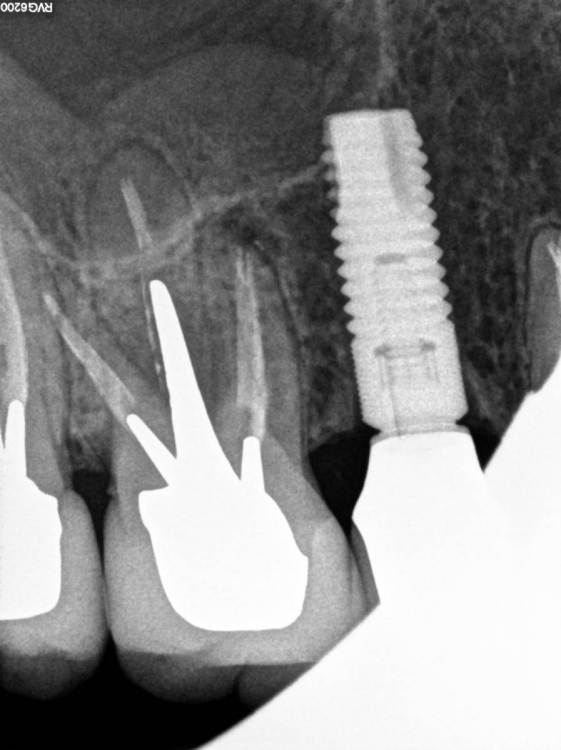

Всем привет!Обострение хронического Pt, ввиду невозможности ортоградной ревизии принято решение об апикальной хирургии.Все манипуляции производятся только под визуальным контролем операционного микроскопа?